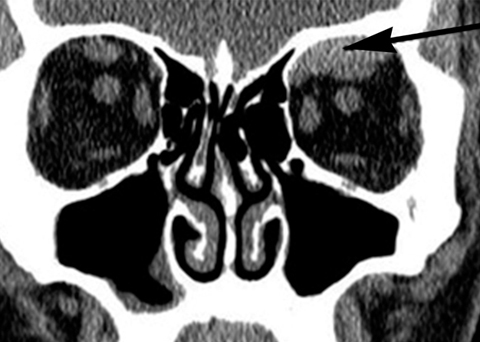

A 64-year-old woman with dilated right pupil, nausea, and headache